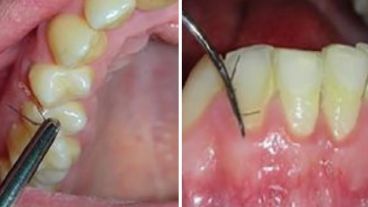

En la consulta realizada a los profesionales de la salud, la paciente se quejaba no solo de la presencia de pelos en la boca, sino también del exuberante vello que le había salido en distintas regiones del mentón y del cuello.

Los especialistas los eliminaron y realizaron un estudio del tejido interno de la boca. Según una investigación publicada en una revista científica, la mujer regresó unos meses después con una presencia aún más generalizada de vello distribuido en las encías de ambos arcos.

La aparición de cabellos en la cavidad oral es un evento extremadamente raro y sus causas son desconocidas. Este es un caso raro de hirsutismo“, sostuvo Khrystyna Zhurakivska, del departamento de Medicina Clínica y Experimental de la Universidad de Foggia y autora principal de la investigación.